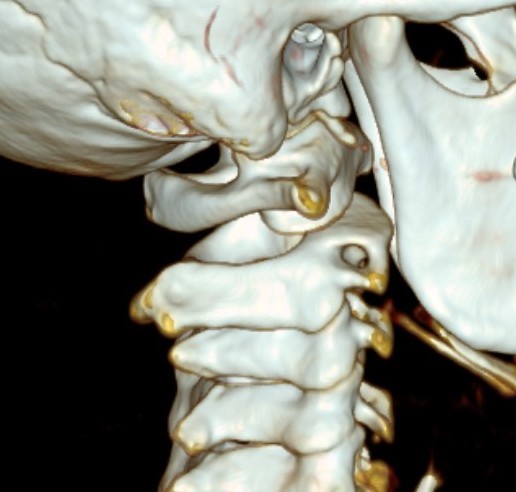

Posterior process fractures

Anatomy

Posterolateral & Posteromedial tubercles

- separated by sulcus for FHL

- lateral larger than medial

PL tubercle

- size variable